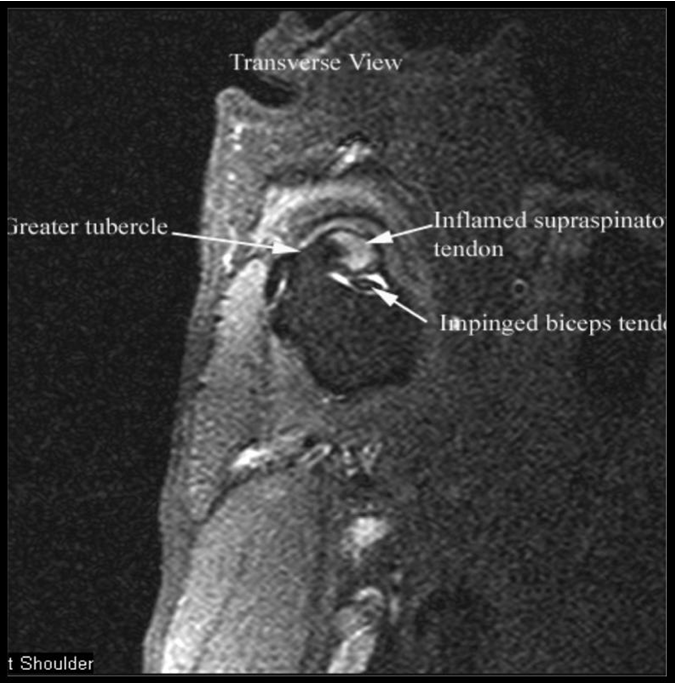

Results: Dogs aged 4 months to 14 years (average 6.5 years; median 6 years) were diagnosed with ST. Performance and sporting dogs were 39.4% of the population, with 58.1% of them being agility dogs. Pain was elicited on palpation of the supraspinatus tendon in 49.3% of dogs. Shoulder radiographs in 283 dogs showed mineralisation in 13% of cases. MRI of the shoulder was performed in 31 cases and revealed findings indicative of ST, including hyperintensity of signal on T1 weighted image (or “spin-lattice”) and Short T1 Inversion Recovery (STIR) sequences of the supraspinatus tendon at its insertion on the greater tubercle and mineralisation of the supraspinatus tendon. Common ultrasonographic findings included increased tendon size (76%), irregular fibre pattern (74%), and non-homogeneous echogenicity (92.5%). The most common findings on shoulder arthroscopy were supraspinatus bulge (82.2%) and subscapularis pathology (62.4%). Elbow pathology was recorded in 54.5% of dogs. Treatment outcomes showed 74.6% of dogs failed to respond to non-steroidal anti-inflammatory drugs (NSAID) and 40.8% failed to respond to rehabilitation.